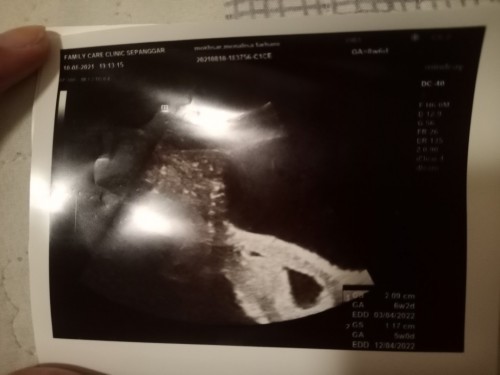

Kantung kosong

hai smua.. nak tnya, normal ka usia kandungan sya spatutnya 8minggu 7hri.. tpi bila scan bru 6minggu 2hri.. tpi kantung masi kosong, tiada apa2.. sya risau sya mngalami kandungan kantung kosong.. stkat ini sya langsung tiada alahan apa2, darah pun tiada kluar lagi.. normal ka kantung still kosong dgn usia kandungan mau masuk 9minggu? π’#bantusharing #firstbaby #pleasehelp #pregnancy